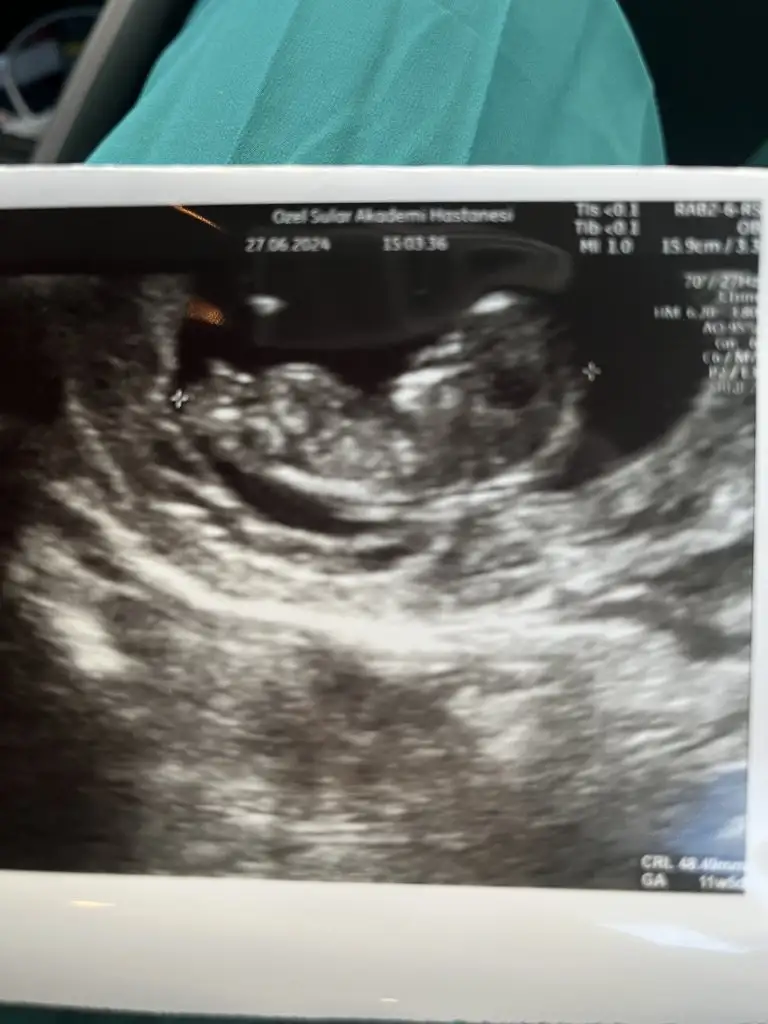

Kızlar selamlar bugün kontrole gittim 1 haftadır üst solunum yolu enfeksiyonu geçiriyordum hiç iyi değildim ama bebişi görünce biraz moralim düzeldi cinsiyetle ilgili hiç yorum yapmadı anlayan çıkar mı aranızda ayrıca haftaya ikili test için çağırdı bizde durumlar böyle 🧡 umarım hepiniz iyisinizdir

Bebişi gördük tepinip duruyordu maşallah 😊😊🧿🧿

Burnuna baktı her şey yolunda dedi ense kalınlığı da 0,90 çıktı . Cinsiyet için de tahminde bulundu erkeğe benziyor ama değişebilir kesin değil dedi .

Amin inşallah 🙏🏻🌹🥰 iki bacak arasını da gösterdi küçücük pipisi göründü . Ama kesin değil dedi .